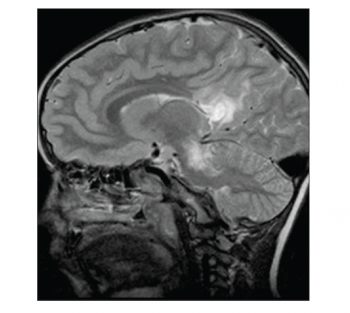

The remainder of the waking record showed no definite epileptiform features. Subsequent magnetic resonance imaging (MRI) of the brain demonstrated extensive diffuse deep white matter high signal change extending inferiorly along the white matter tracts as far as the superior aspect of the pons and brain stem on axial fluid attenuated inversion recovery (FLAIR) and axial T2-weighted sequences.

Extensive high signal changes were seen in the posterior corpus callosum. These extensive changes were bilateral and symmetrical showing moderate peripheral rim enhancement post-gadolinium administration.